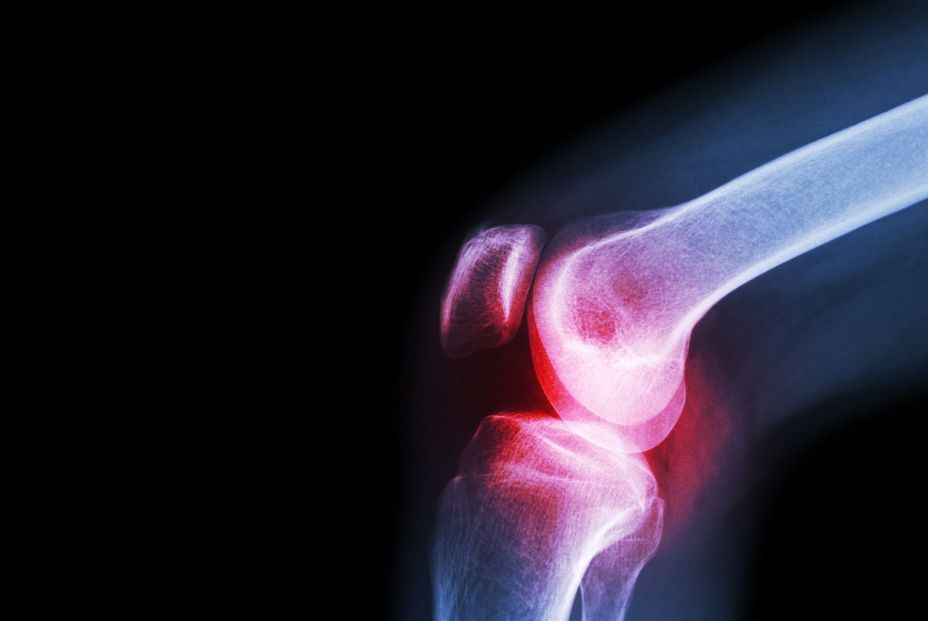

La artritis representa un importante problema de salud pública, que afecta a aproximadamente 595 millones de personas (7,6% de la población mundial) y contribuye significativamente al deterioro de la calidad de vida en la edad adulta. como documenta un estudio en ‘Lancet Rheumatology’.

La osteoartritis (OA) y la artritis reumatoide (AR), los dos tipos más comunes de artritis, a menudo se consideran pertenecientes a la misma categoría de enfermedades, ya que ambas afecciones implican dolor e inflamación en las articulaciones.

Sin embargo, ambas patologías presentan una fisiopatología, síntomas, causas subyacentes y modalidades terapéuticas distintas, como demuestran algunas investigaciones, como demuestran algunas investigaciones. Hasta la fecha, el diagnóstico de la artritis sigue siendo un desafío debido a la falta de una única prueba definitiva. El diagnóstico de la OA actualmente utiliza una combinación de enfoques basados en cuestionarios para evaluar los síntomas clínicos y pruebas de imagen, que incluyen radiografías, ecografías y resonancias magnéticas, como se documenta en 'Annals of Translational Medicine'.

.Mientras tanto, el enfoque diagnóstico para la AR también requiere pruebas de laboratorio como análisis de muestras de sangre. Si bien los métodos de biopsia líquida suelen demostrar una sensibilidad y especificidad clínicas del 70% al 80%, presentan limitaciones para discriminar a los pacientes en fases tempranas de la enfermedad. A pesar de estos enfoques, la sutileza de los síntomas iniciales y la superposición de criterios diagnósticos dificultan la distinción entre OA y AR. Además, algunos pacientes pueden tener dificultades para determinar si su dolor se debe a procesos inflamatorios o deformidades articulares estructurales. Por lo tanto, distinguir con precisión entre el dolor causado por la inflamación sinovial activa, característica de las enfermedades reumáticas, y el dolor resultante del estrés mecánico y la degeneración del cartílago es crucial para optimizar las estrategias de tratamiento y monitorear la progresión de la artritis.